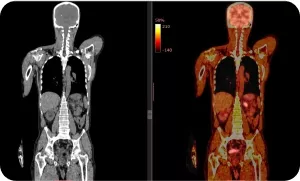

ПЭТ/КТ всего тела с 18-ФДГ является адекватным и высокоинформативным методом первичной диагностики и мониторинга изменений в скелете при опухолях, тропных к 18F-ФДГ. При оценке эффективности противоопухолевого лекарственного лечения методом ПЭТ/КТ с 18F-ФДГ особенно у пациентов с множественными метастазами не только в костях, но и в различных органах, рекомендуется использовать критерии PERSIST и вывод о прогрессировании со стороны метастазов в скелете делать только при выявлении новых очагов в сочетании с повышением уровня накопления РФП на ПЭТ в прогрессирующем очаге по данным КТ. Критериями ПЭТ-ответа при солидных опухолях (по критериям PERCIST) является снижение метаболической активности максимально активного метастаза в кости на 30% и более.

Если по результатам ПЭТ/КТ определяется изолированное изменение активности накопления РФП в ранее имевшихся очагах, то возможно интерпретировать это как процессы репарации.

ПЭТ/КТ всего тела с 18-ФДГ является адекватным и высокоинформативным методом первичной диагностики и мониторинга изменений в скелете при опухолях, тропных к 18F-ФДГ.

Image

ПЭТ КТ всего тела с 18-ФДГ

При оценке эффективности противоопухолевого лекарственного лечения методом ПЭТ/КТ с 18F-ФДГ особенно у пациентов с множественными метастазами не только в костях, но и в различных органах, рекомендуется использовать критерии PERSIST и вывод о прогрессировании со стороны метастазов в скелете делать только при выявлении новых очагов в сочетании с повышением уровня накопления РФП на ПЭТ в прогрессирующем очаге по данным КТ. Критериями ПЭТ-ответа при солидных опухолях (по критериям PERCIST) является снижение метаболической активности максимально активного метастаза в кости на 30% и более.